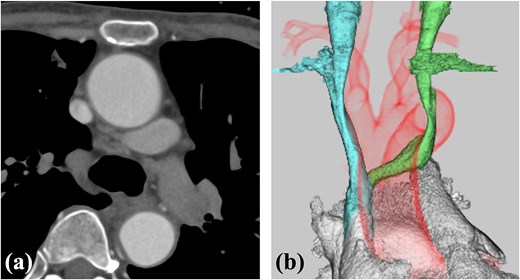

A 78-year-old woman with severe mitral regurgitation (MR), tricuspid regurgitation, and atrial fibrillation was admitted with worsening heart failure. She had hypertension, but no known CHD. She was 138 cm tall, weighing 34.6 kg, with a body mass index of 18.3 kg/m2. Her vital signs were normal. The N-terminal fragment of pro B-type natriuretic peptide was elevated at 2577 pg/mL. Chest radiography revealed cardiac enlargement and bilateral pulmonary edema. Transesophageal echocardiography (TEE) revealed shortening of the anterior and posterior leaflets of the mitral valve, with thickening of the commissure, indicating severe MR (Fig. 1 and Video 1). The tricuspid annulus diameter increased to 29.4 mm. No congenital heart diseases were detected. Contrast-enhanced computed tomography (CT) revealed that the left innominate vein coursed posterior to the ascending aorta, the so-called ALBCV, and joined the superior vena cava (SVC) 3 cm from the right atrium (Fig. 2 and Video 2). Venography of the left upper limb confirmed the ALBCV (Fig. 3 and Video 3). No communication existed between the ALBCV and the coronary sinus.

Venography of the left upper limb. The ALBCV joined the SVC, and no communication was observed between the ALBCV and coronary sinus.